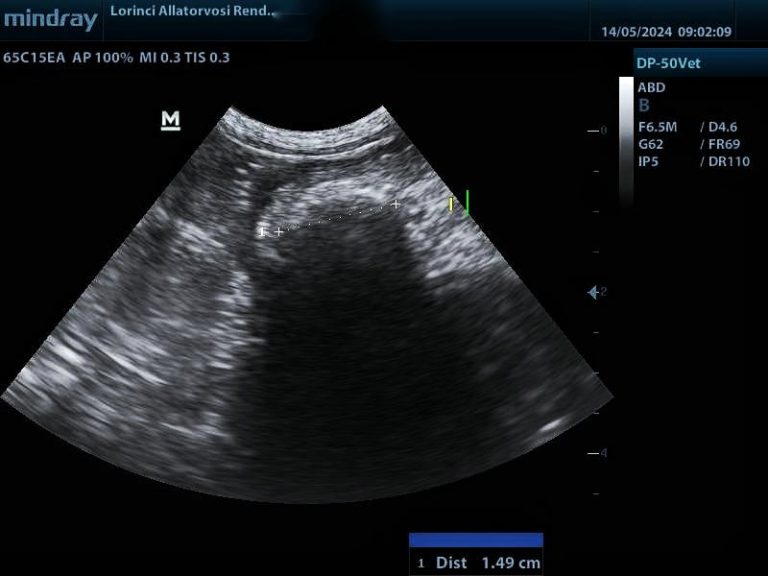

Hasi ultrahang vizsgálat során hasonló elváltozásokat láthatunk mindkét betegségtípusnál. A gyomor és belek fala több rétegből áll és ezek eltérő mértékben vastagodhatnak meg a különböző betegségekben. Limfóma esetén rendszerint az izomréteg, gyulladásnál általában a nyálkahártya válik vaskosabbá, de sajnos ez nem minden esetben történik így, különben könnyű lenne a gyulladásos és daganatos folyamatokat elkülöníteni egymástól.

Gyulladás miatt megvastagodott izomréteg